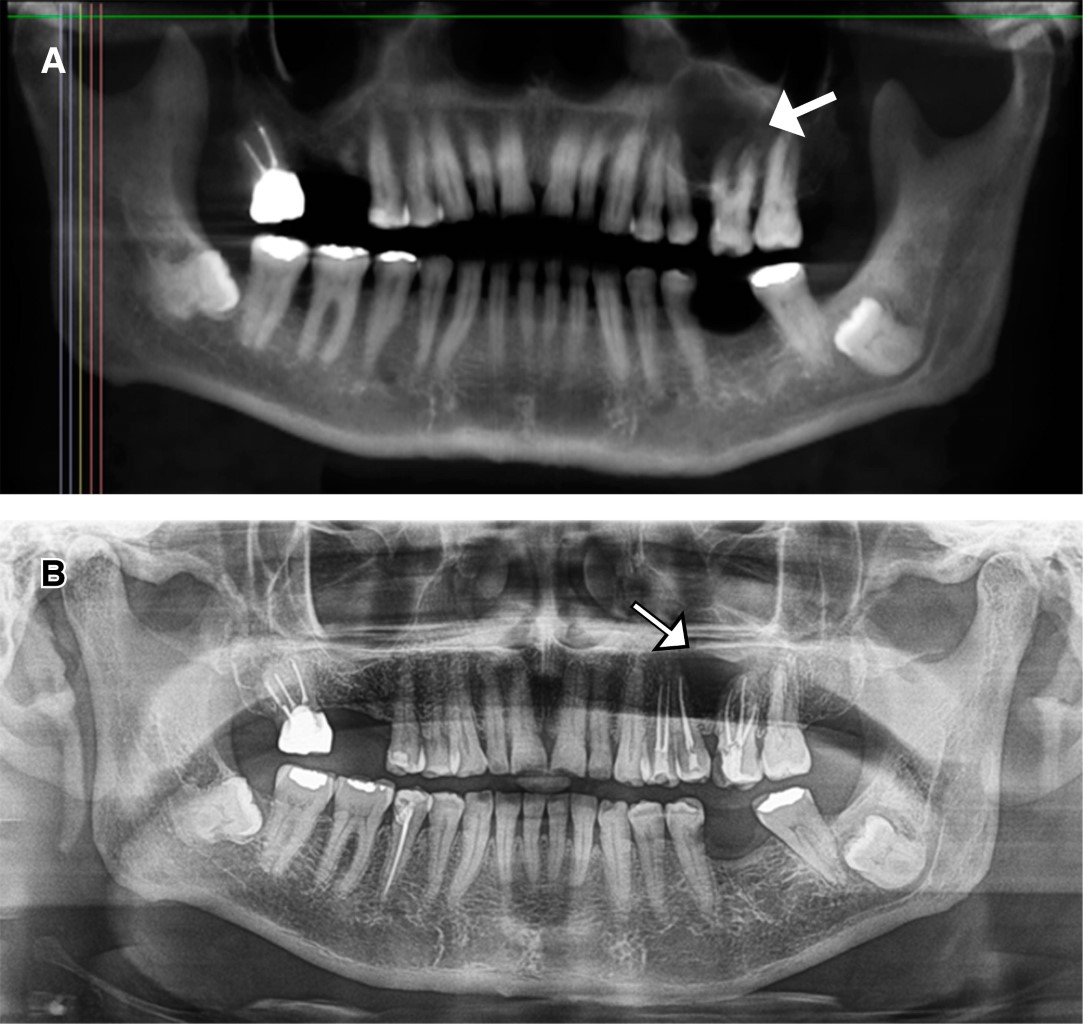

Reporte de caso inusual de queratoquiste odontogénico esporádico maxilar

El queratoquiste odontogénico (OKCs) es una enfermedad rara que se manifiesta en la región maxilofacial, afecta principalmente a la mandíbula más que al maxilar y se asocia con la presencia de un diente retenido. La mayoría de los casos son asintomáticos, afecta más a hombres que a mujeres en su segunda década de vida; los pacientes pueden presentar dolor o hinchazón de tejidos blandos en los OKCs infectados. La expansión ósea y la parestesia de los labios se registran en menos casos. La región más común en los maxilares es el tercer molar y la región canina. El objetivo de este informe es presentar un caso clínico infrecuente de un varón de 72 años con CCO asintomáticos en región maxilar izquierda, que presenta lisis ósea en región vestibular y palatina con aleación de fosas nasales sin comprometer los dientes. El paciente fue tratado con enucleación y osteotomía periférica mediante instrumento rotatorio; actualmente sin recidiva. También se realiza una revisión de casos con queratoquiste maxilar.

Figura 1

Figura 2